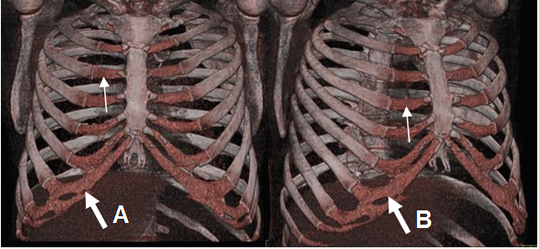

Fig 1. Costillas normales.

A y B: TAC reconstrucción 3D. Costillas verdaderas que se unen directamente al esternón (Flechas delgadas) y falsas cuyos cartílagos se fusionan. (Flechas gruesas).